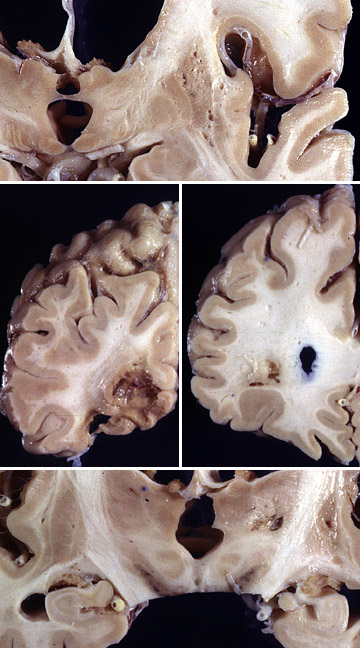

Grossly, this composite view of the brain demonstrates multiple remote cystic infarcts in various locations. This process took several years.